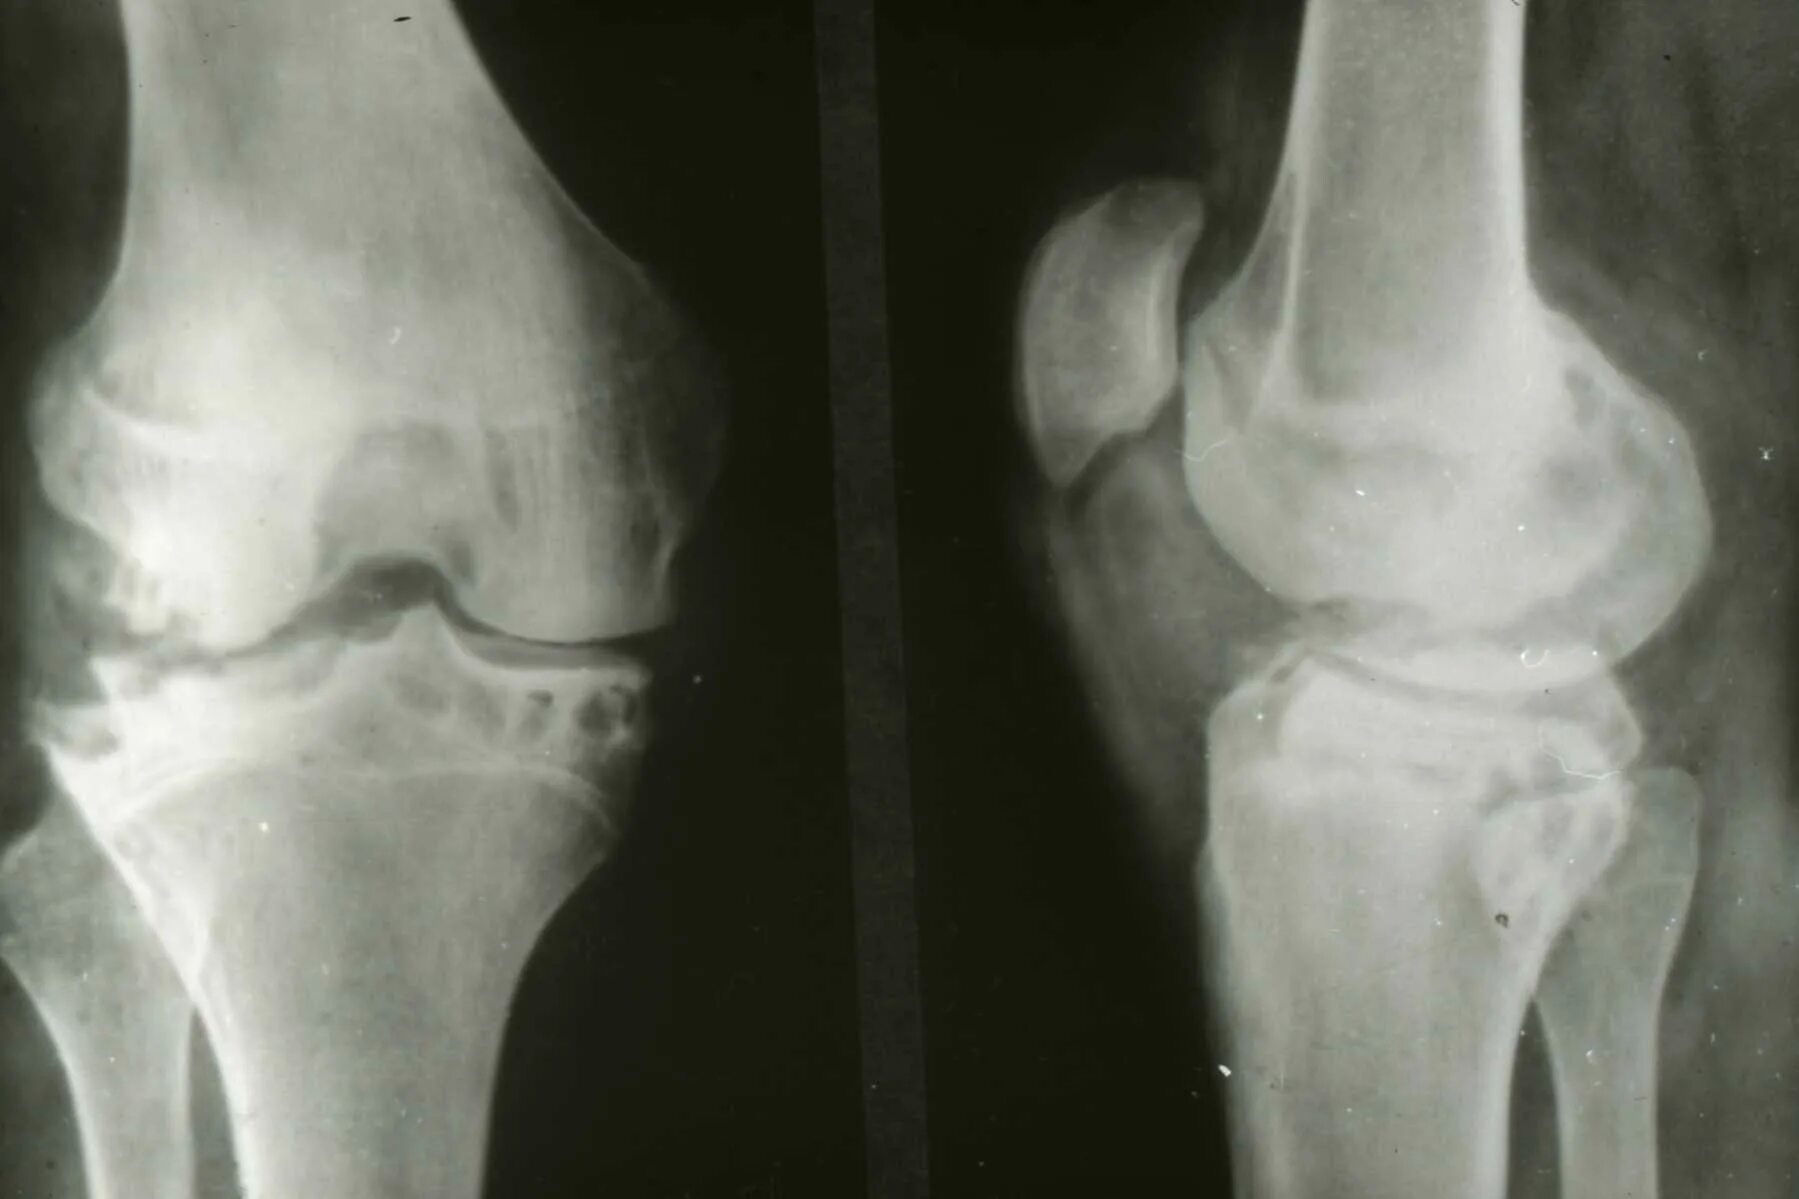

Туберкулез суставов симптомы